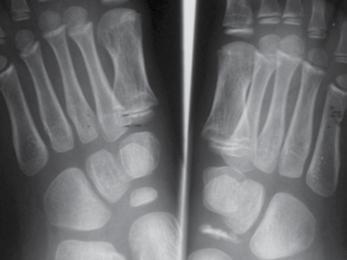

5-årig pojke som sedan en månad haltat och verkat ha ont i höger fot. Inget trauma, ingen feber eller infektion. CRP u.a.

Pojken verkar frisk men går med hälta och vill inte avveckla steget riktig med höger fot. Vid klinisk undersökning finner man måttlig ömhet över mellanfoten. Rörelseomfånget i fotleden och subtalärt är normalt.

Rtg , v.g. se bild.

a. Diagnos? ( 1p)

b. Behandling ? (1p)

c. Naturalförlopp ?(1p)

Fråga 9.

a. Mb. Köhler 1 ( avaskulär nekros av os naviculare)

b. Hålfotsinlägg eller en tids behandling med gånggips brukar lindra besvären, som försvinner inom några månader.

c. Till skillnad från avaskulära nekroser på andra lokalisationer restitueras konfigurationen av os naviculare spontant. Röntgenbilden normaliseras inom loppet av några år och sjukdomen ger inga sena komplikationer.